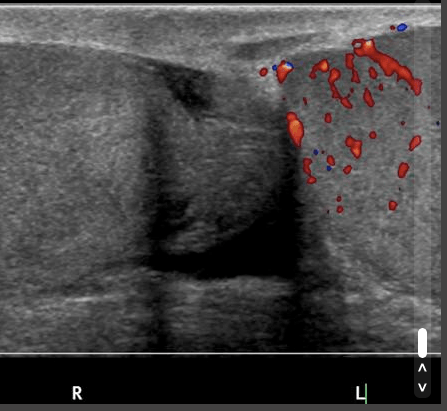

USS is especially useful in patients with sudden onset pain to assess for Testicular Torsion (no flow on colour doppler in many cases) and to assess for Epididymo-orchitis (increased flow in many cases)

Ultrasound 1 Epididymo-orchitis – “Testicular US demonstrates increased vascularity in the left testis and epididymis in keeping with epididymoorchitis. There is also a left sided hydrocele.